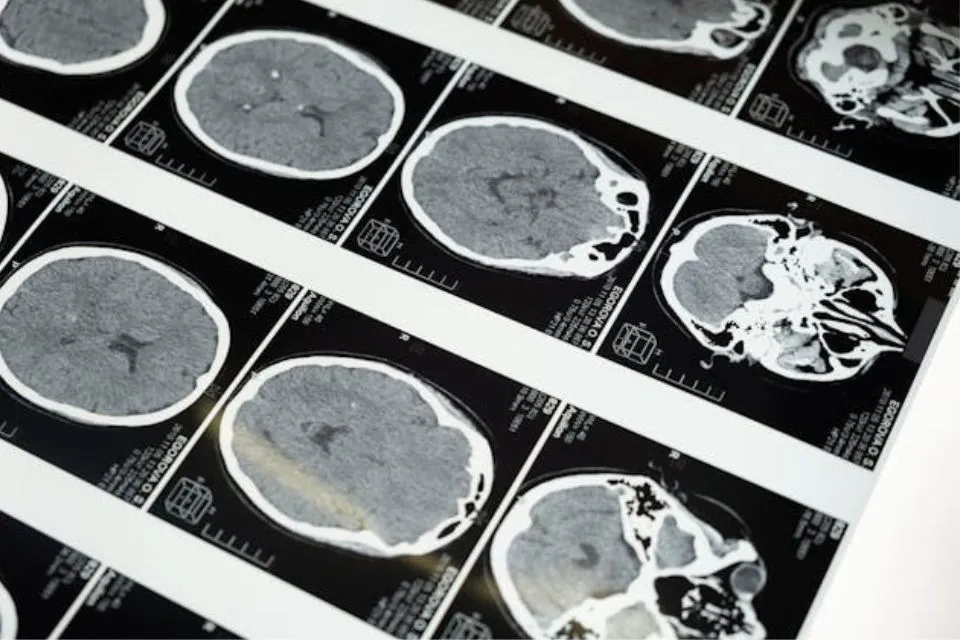

Para lograrlo, cuentan con el producto “Telepathy”, un chip cerebral inalámbrico que permitiría la comunicación por ‘telepatía’ con el computador o con algún otro software externo. Para esto incluso se ha pretendido lograr unir la tecnología robótica con este chip y lograr que el ser humano incremente sus capacidades. Por ejemplo, una persona cuadripléjica podría valerse de una prótesis robótica y controlarla vía sondas cerebrales.

La empresa cuenta con un robot especializado para realizar la cirugía del implante de Telepathy, el chip cerebral. En su página web (www.neuralink.com) especifica las partes del mismo y su funcionamiento. Argumentan que, debido a que los hilos del implante son aún más finos que un cabello humano, no es posible valerse de una mano humana para la cirugía. Por lo que el robot se encarga de ese trabajo.